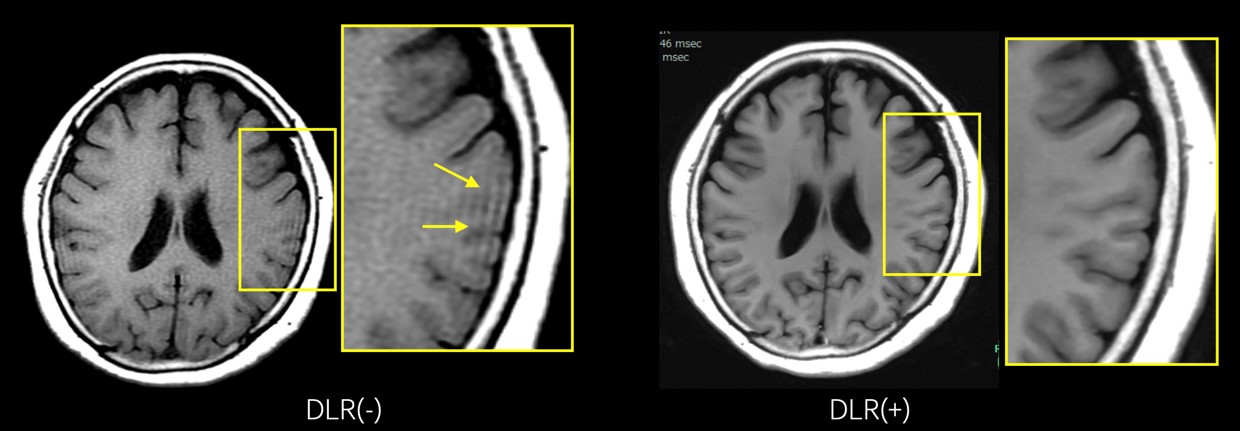

AIR™ Recon DLのアーチファクト対策

AIR™ Recon DLによってトランケーションアーチファクトを目立たなくすることが可能です。図5は頭部のT1強調画像ですが、AIR™ Recon DLによって脳辺縁に沿った線上のトランケーションアーチファクトが軽減されています。

VictorLiftUpgrade_Kitakyushu08.jpg

図5: 頭部T1WI DLRによるトランケーションアーチファクトの低減